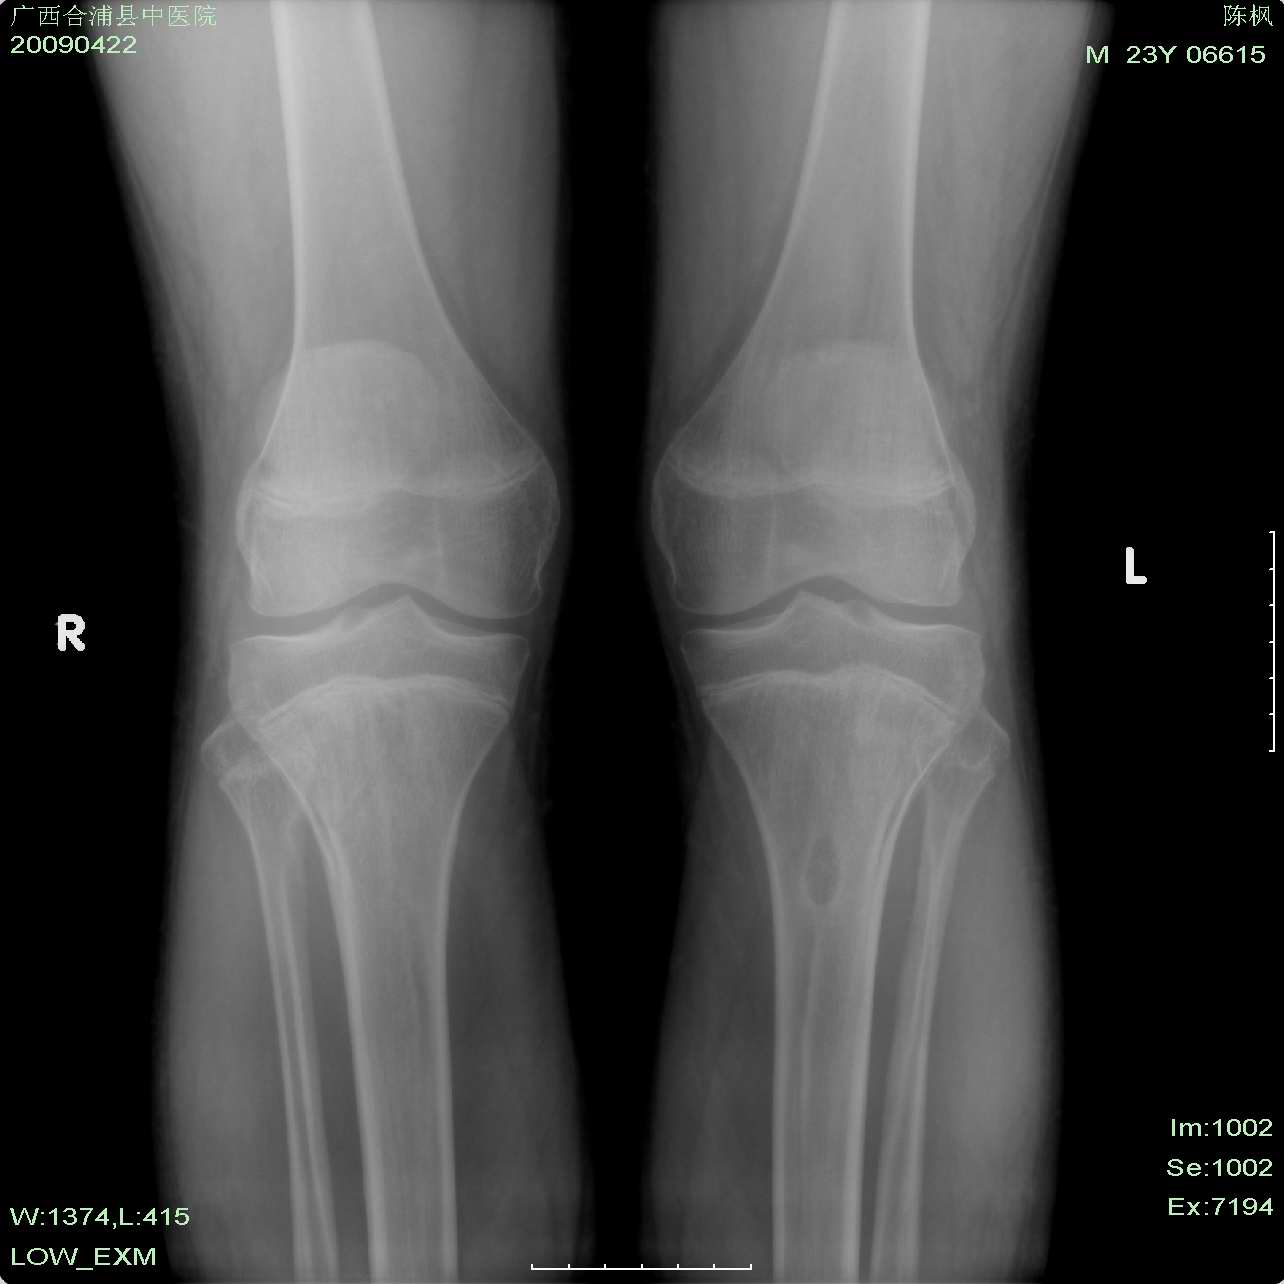

以下是引用杀毒软件在2009-4-22 19:28:00的发言:[br]长骨增粗见骨膜性成骨,多个骨骺线未闭,骨质疏松,左胫骨内卵圆形透亮区,边缘硬化。[br][br]结合临床符合----垂体内分沁骨病。可惜现有资料诊断并不具特征性。 [br][br]加照---蝶鞍和颅盖看看[br][br]胫骨内卵圆形透亮区---考虑---纤维性骨皮质缺损可能性大,不完全排除----低毒感染

以下是引用余辉在2009-4-22 20:41:00的发言:[br]患者23岁,骨骺未闭合,有垂体瘤手术史,提示垂体前叶功能低下,生长激素分泌低下,骨龄延迟.[br]所示各骨密度减低,下部腰椎侧弯,双侧股骨颈弯曲,且似有looser带,股骨头二次骨化中心内似有囊状影重叠,左侧胫骨髁间嵴及胫骨上干骺端见囊性改变.胫骨干皮质有分层,提示骨质软化,纤维囊性骨炎及骨膜功能异常等.[br]此为患者垂体整体功能低下(前后叶均功能低),对内分泌调节作用就低下,会使各种内分泌激素均产生紊乱,所以本例内分泌改变是混合性的,骨骼改变由多种内分泌异常引起,至少符合甲旁减\\甲旁亢\\肾上腺皮质功能亢进\\雄激素分泌异常等改变[br][br][本贴已被 余辉 于 2009-4-22 20:43:08 修改过]